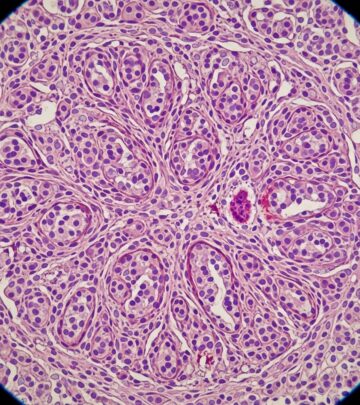

Radiographic Investigations In Melanoma: Essential Imaging Guide